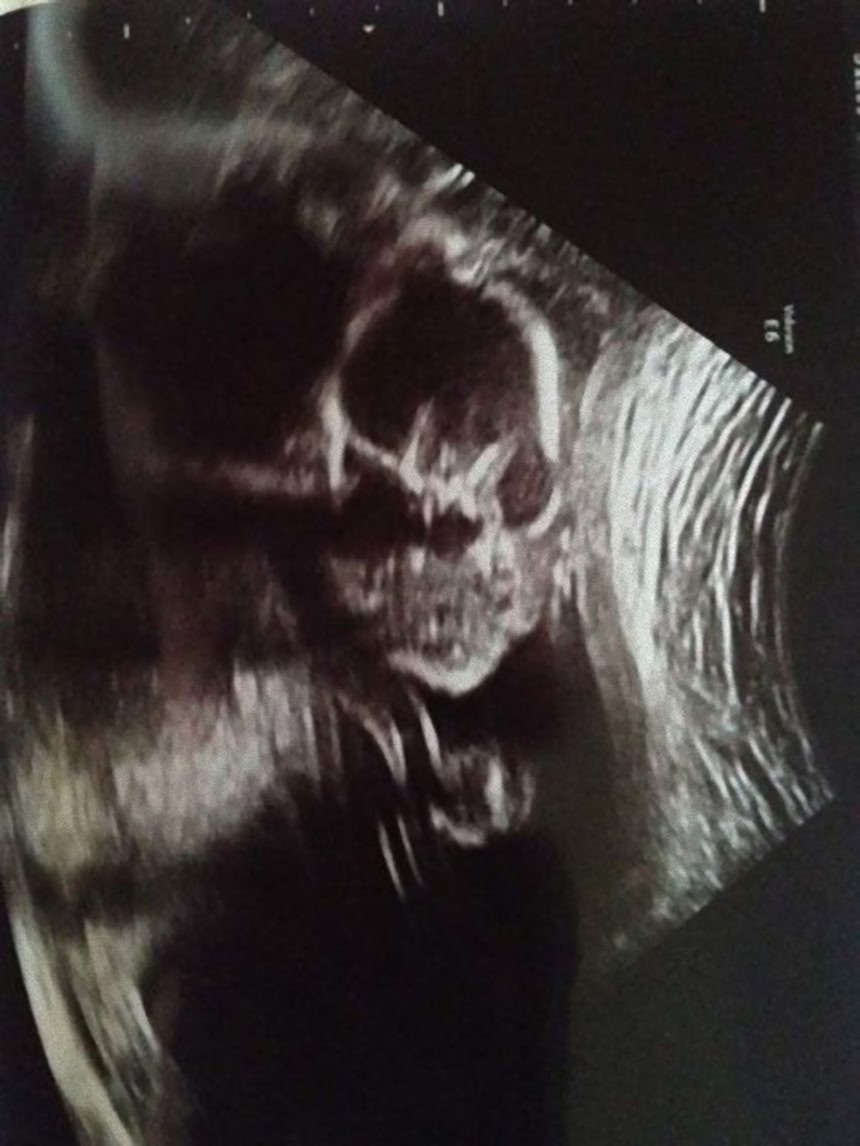

人間の脳は、3つの点が集まった図形を人の顔と見るようにプログラムされているようにできている。これはシミュラクラ現象と呼ばれるものなのだが、モノクロで撮影された胎児の超音波写真は、見方によってはホラーとしか言えない悪夢的光景が潜んでいるようなんだ。

これらの超音波写真は、親御さんがネット上で公開したもので、見方によっては腹にやばいものが宿っているように見えるものだ。

実際には断面図だから骸骨っぽくなっちゃうんだよね

瞼が出来るまで魚のように目見開いたままだし口がまだ三口でエイリアンの様な顔なんね、正面からは自分の子供でも顔は見たくないなぁ